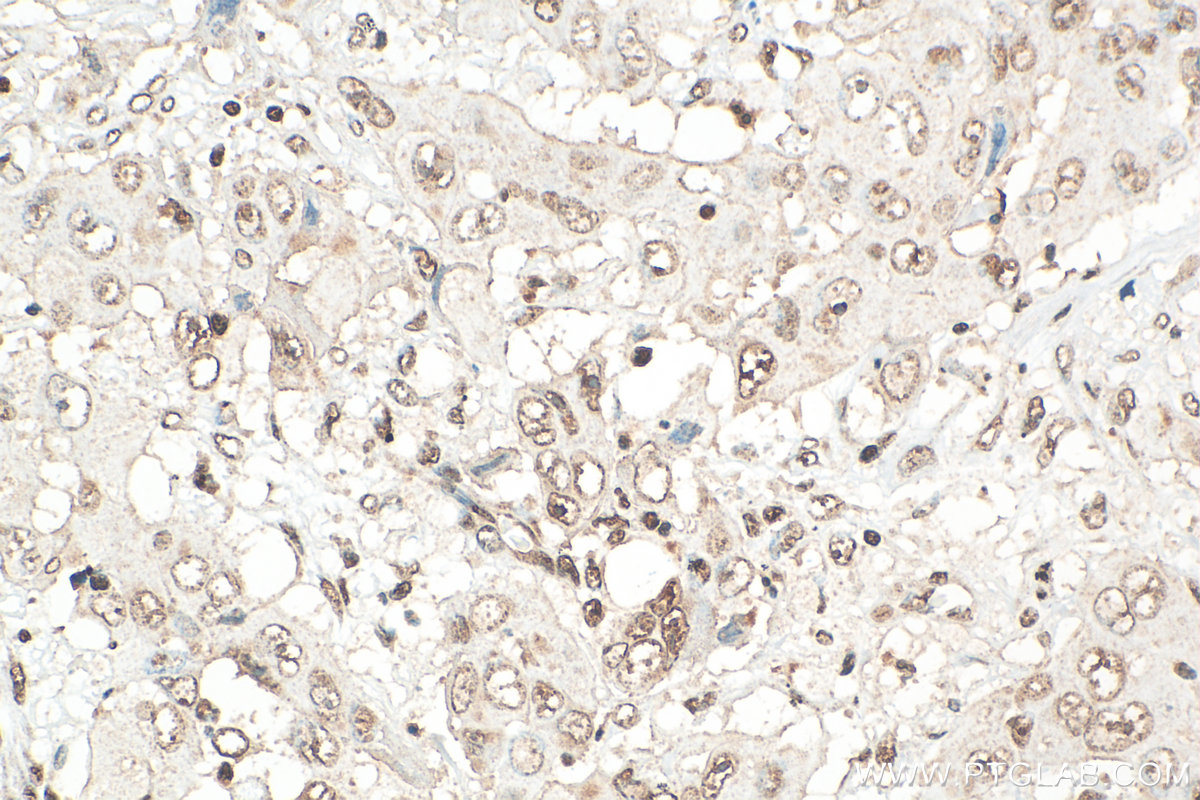

| Positive IHC detected in | human lung cancer tissue Note: suggested antigen retrieval with TE buffer pH 9.0; (*) Alternatively, antigen retrieval may be performed with citrate buffer pH 6.0 |

| Immunohistochemistry (IHC) | IHC : 1:500-1:2000 |